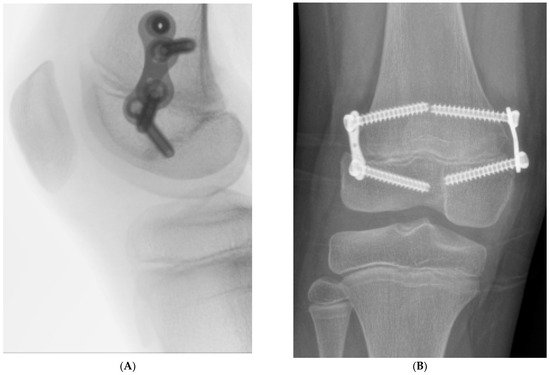

Weight-bearing was permitted on the day of surgery, and all patients were discharged either the same day or the following day. Routine follow-up examinations were performed in the outpatient clinic two to three weeks postoperatively, with subsequent visits every three months. The screws and 8-plates were removed once the plates changed orientation from oblique to vertical relative to the long axis of the bone, indicating that the plate had reached its maximum corrective effect (Figure 2).

Figure 2. Radiographs showing the 8-plates in a horizontal orientation, with (A) representing the lateral view and (B) representing the anteroposterior (AP) view, indicating the end of their correction potential in the RGG process.